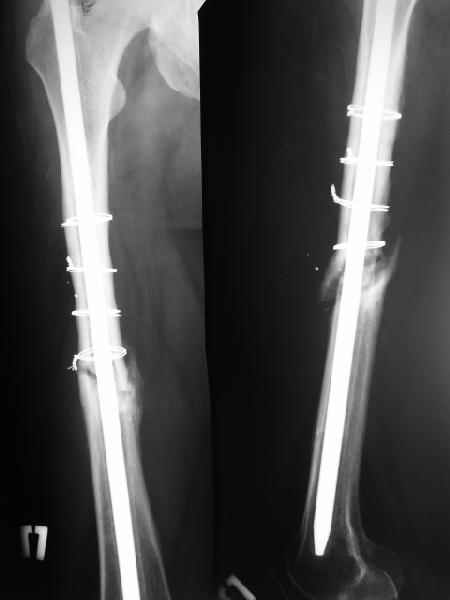

В районной больнице больному выполнен остеосинтез обоих бедер штифтом Кюнчера и накостный остеосинтез правой плечевой кости. Через год больной поступил к нам с ложным суставом шейки левого бедра, обеих бедер и правой б/б кости. Нами выполнено остеосинтез правой голени и левого бедра пластиной Абдуразакова (угольникообразная пластина) с аутокостной пластикой (трансплантат 1/3 ширины малоберцовой кости, длиной 12-14 см.). Через 6 месяцев в связи жалоб больного на хруст, боль и не возможность сидеть, больному произведено цервикокапитальное эндопротезирование головки левого бедра. Больной не посоветовавшись с нами, активно стал разрабатывать левый коленный сустав, в результате через 3 месяца после последней операции поступил с изломом пластины (рис.1). На наш взгляд, оптимальным решением было выполнение остеосинтеза блокирующими гвоздями обеих бедер (рис2). Это первые операции с использованием подобных гвоздей (получили по гум.помощи), поэтому практики по использованию их у нас нет.1. используются ли эти гвозди при ложных суставах?2. Больной в течение этих лет не ходит, можно ли его ставить на ноги?3. Как вести дальше этого больного?4. Какие возможно были варианты остеосинтеза, кроме реэндопротезирования ревизионной ножкой?Заранее благодарю, Алишер.

На данный момент правая голень срослась, больной активен в пределах постели. Второе(правое) бедро стабилизированное (рис. до и после). движения в коленном суставе: сгибательная контрактура правого коленного сустава 90, левого 145.